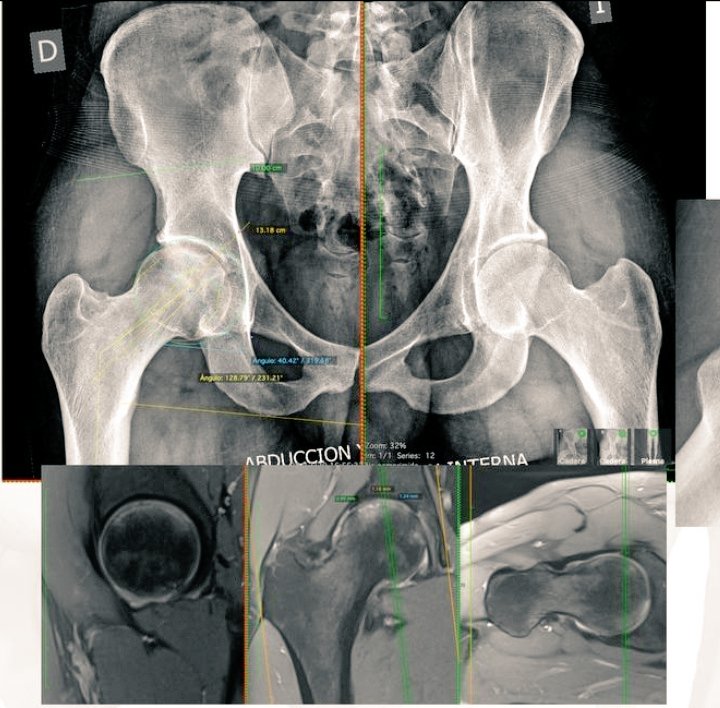

29 yo Male Right Hip ON Total Hip RESURFACING #recons #orthotwitter #adultrecons @caderarodilla #DrDarioGarin Tboughts @DrLeeRubin @hugortopedista @generalorthomd When arthroscopy? When arthroplasty?

RPURATA's tweet image. 29 yo Male

Right Hip ON

Total Hip RESURFACING

When arthroscopy?

When arthroplasty?